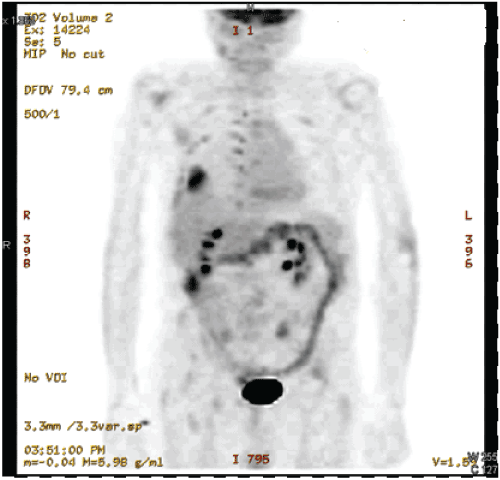

Figure 3: PET scan showing 4.2 cm right lower lobe mass with FDG avid pleural, extra pleural, pancreatic and osseous lesions.